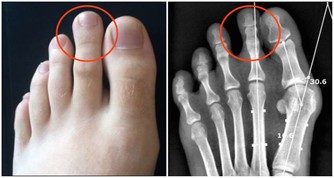

因為評估後這顆痘痘實在是太大了,

醫生不得不用手術刀將頭皮劃開,才能成功擠出這顆超巨大痘痘。

是不是超刺激的!竟然從頭皮裡冒出一個「角」,

接著一整顆痘痘就在一瞬間被擠了出來,我彷彿可以聽見隱藏的「噗滋」聲…。

而最後在成功擠出這顆痘痘後,醫生開始做一件事-縫合。

因為這顆痘痘的尺寸實在是超乎想像的大,

為了頭皮的切口癒合著想,不得不用針把傷口縫好。